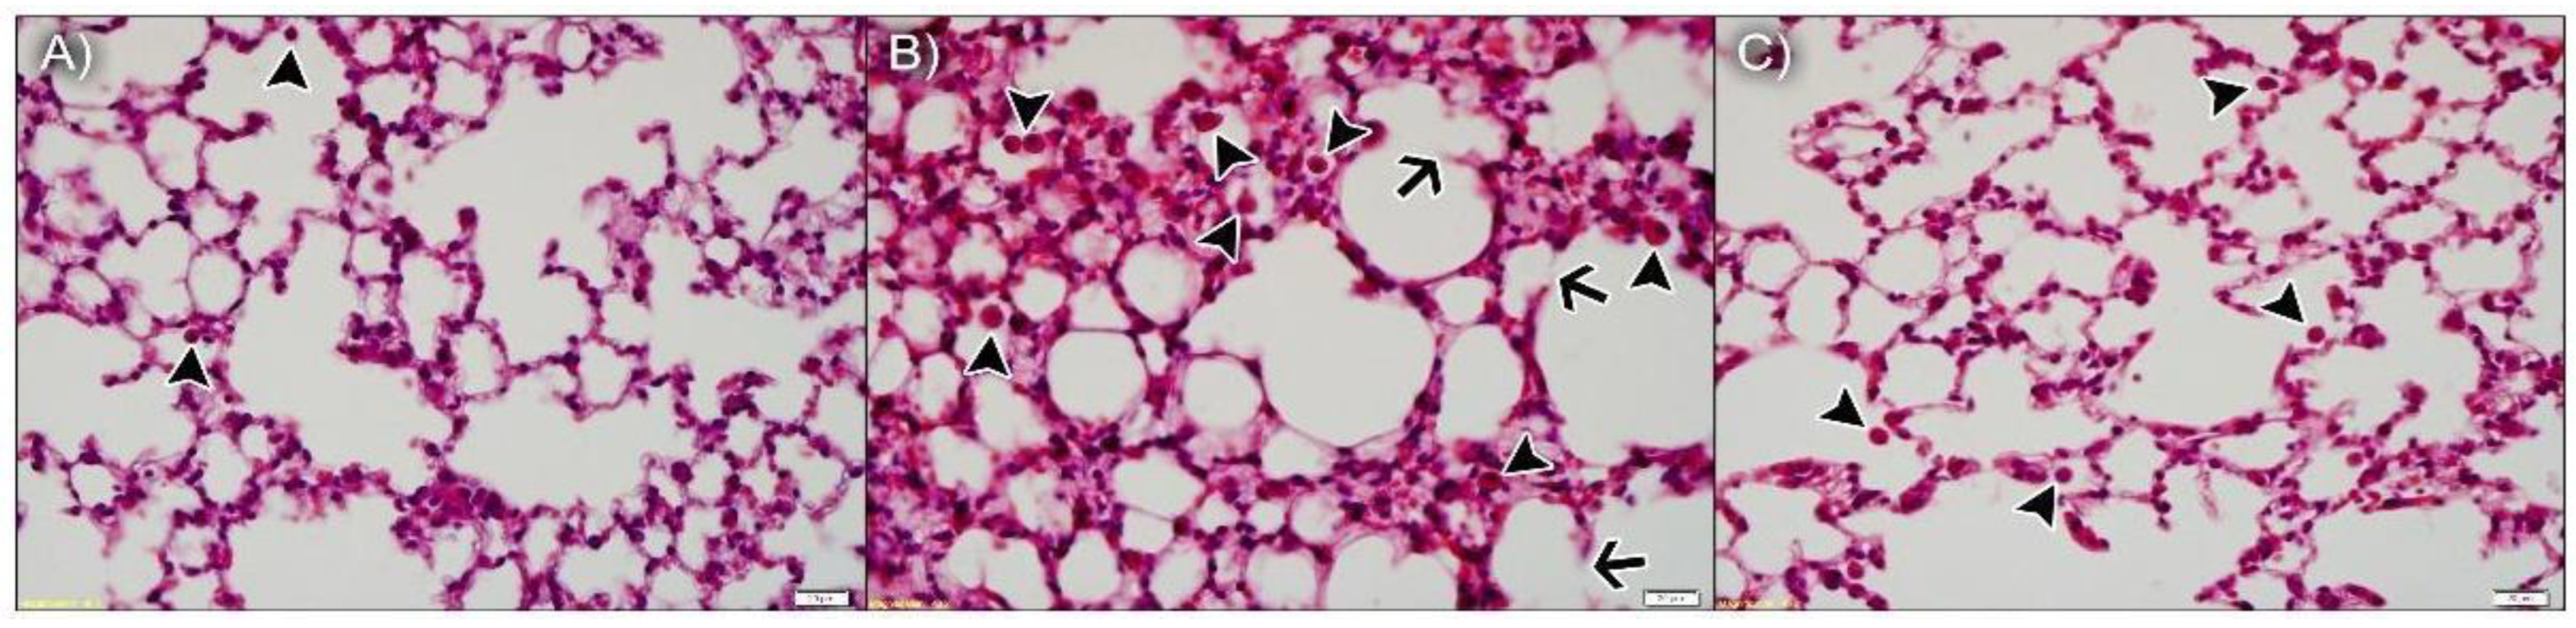

3.3.1. npBX Preserves Pulmonary Histoarchitecture